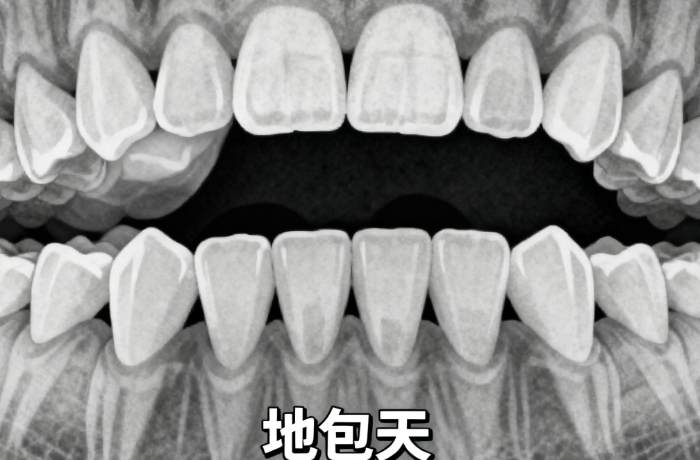

- 矫正难度:轻度牙列不齐(如个别牙拥挤)费用偏低,约8000-15000元;重度畸形(如较重龅牙、地包天需骨钉辅助)费用上涨,加骨钉需额外800-3000元/颗。

- 儿童较重骨性畸形(如较重地包天)可凭诊断证明报销部分费用(约10%-30%)